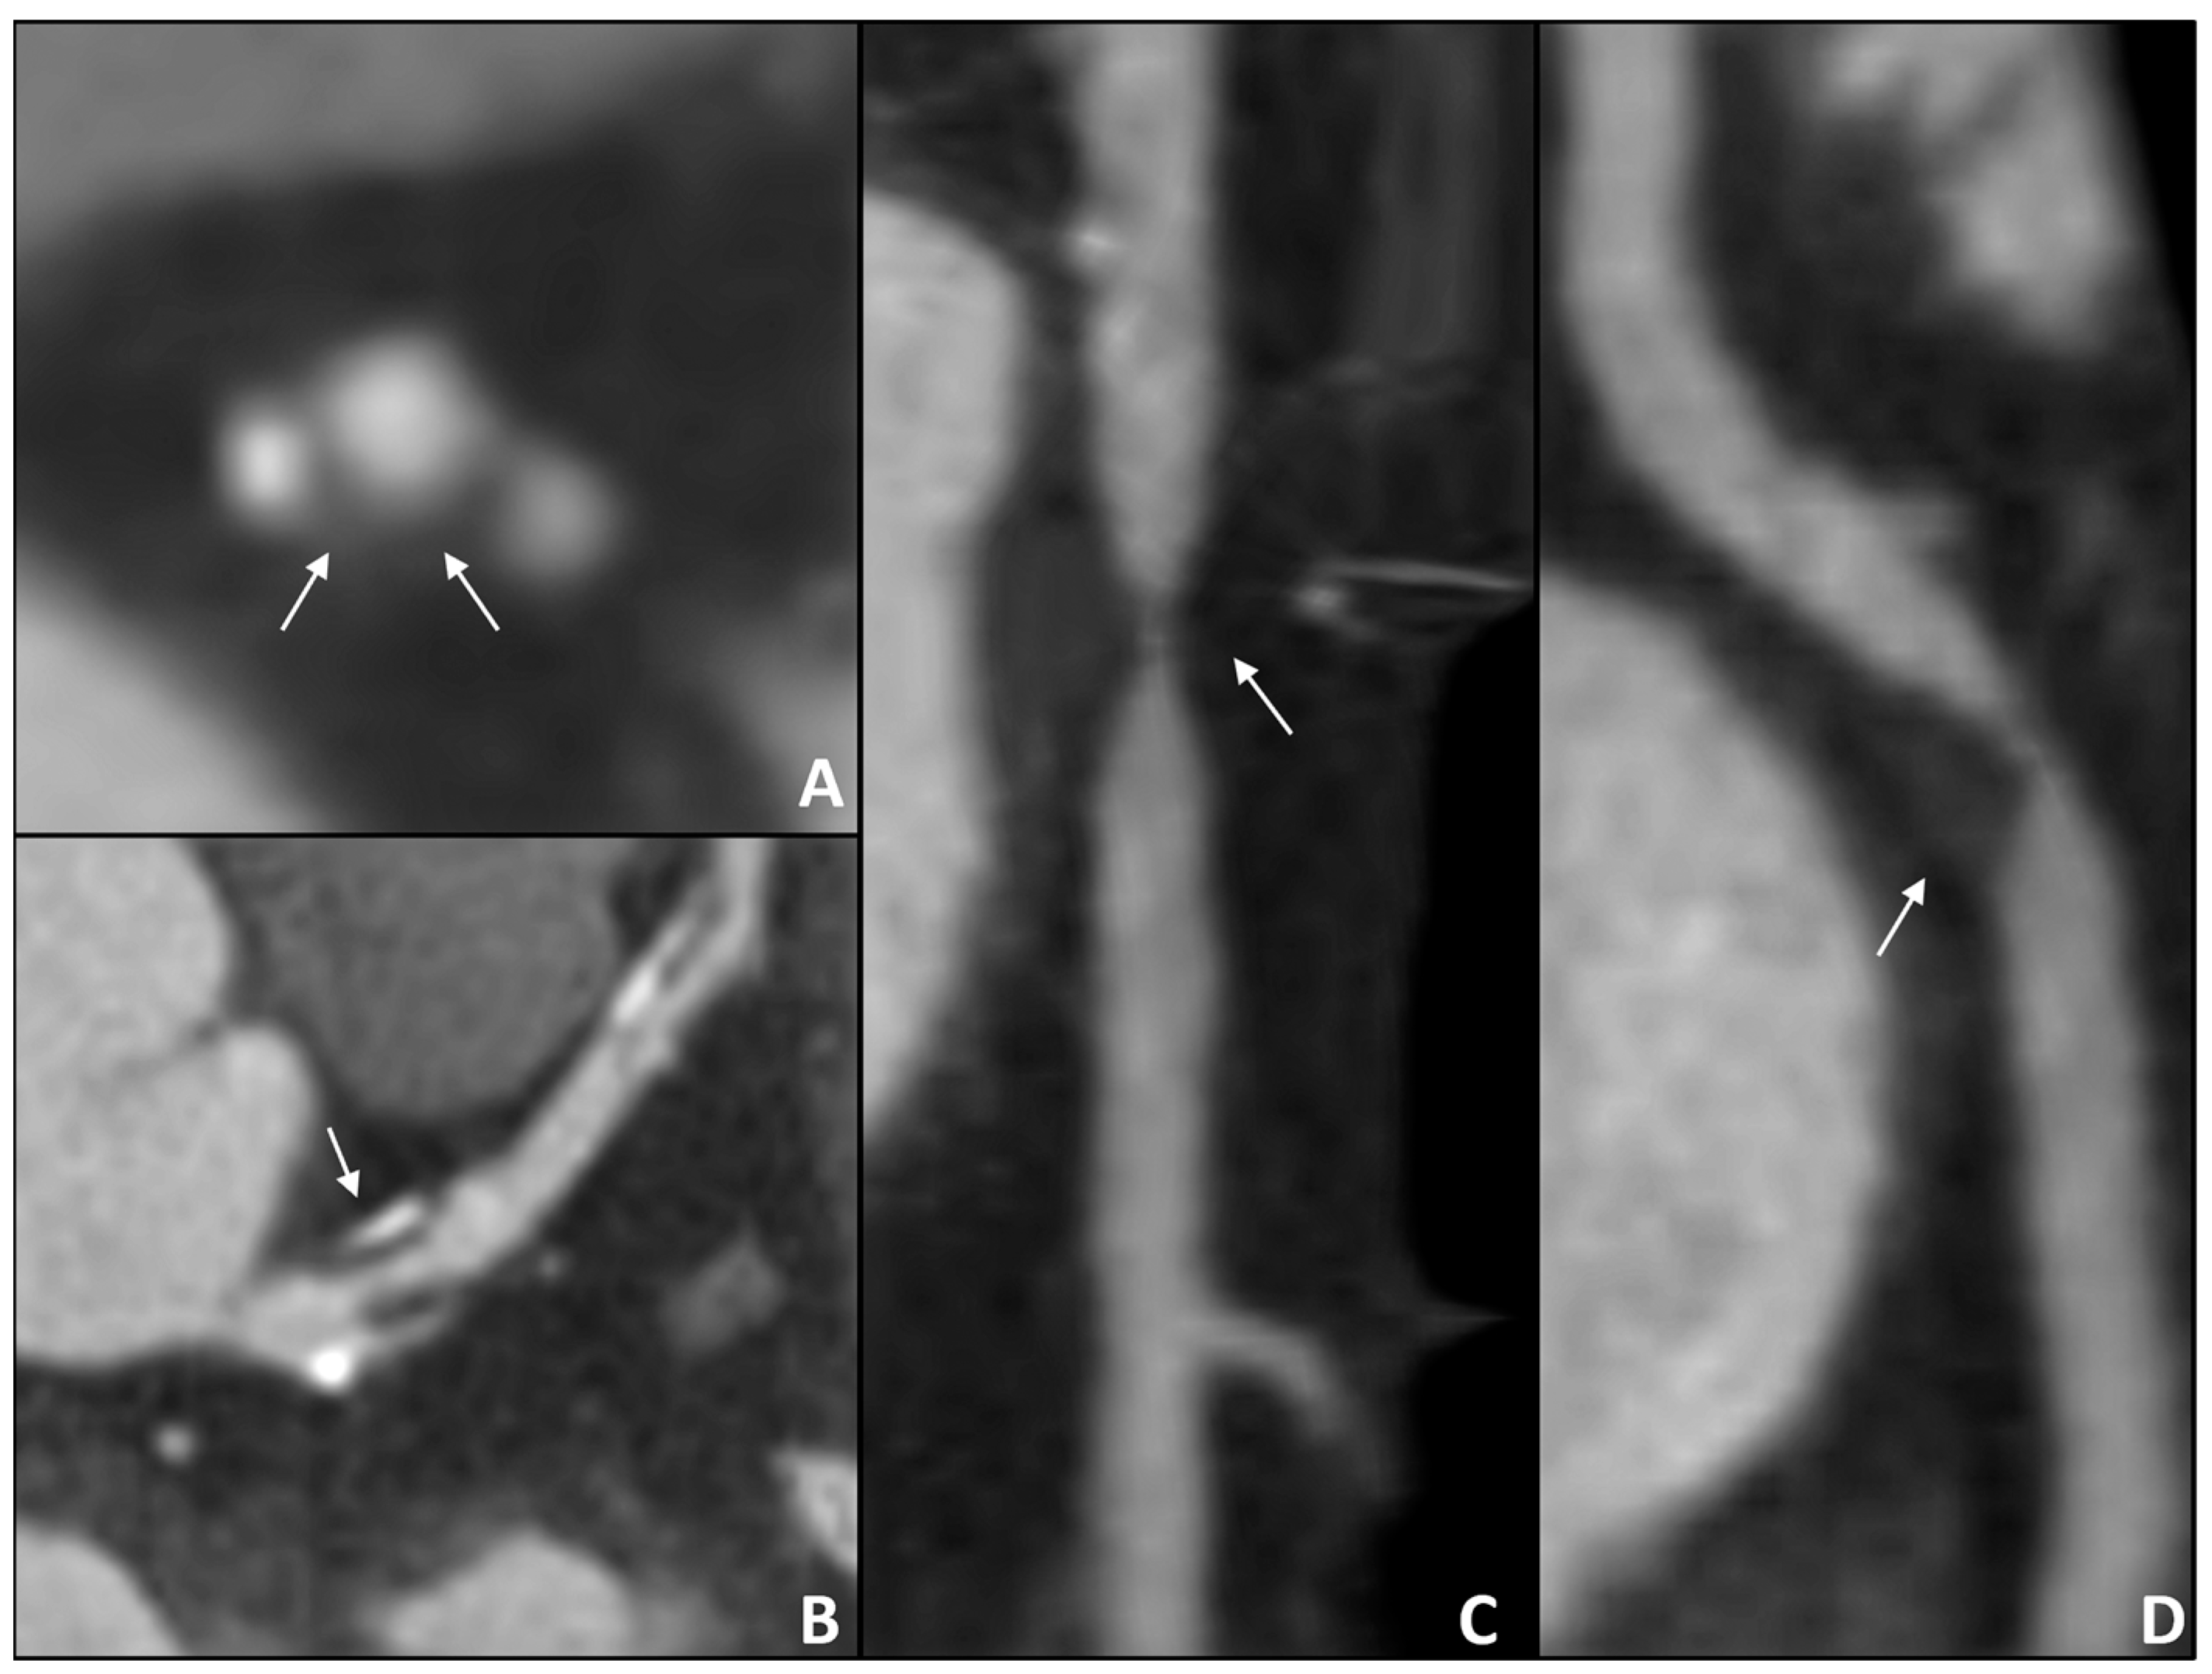

- Kral, B.G.; Becker, L.C.; Vaidya, D.; Yanek, L.R.; Qayyum, R.; Zimmerman, S.L.; Dey, D.; Berman, D.S.; Moy, T.F.; Fishman, E.K.; et al. Noncalcified Coronary Plaque Volumes in Healthy People With a Family History of Early Onset Coronary Artery Disease. Circ. Cardiovasc. Imaging 2014, 7, 446–453. [Google Scholar] [CrossRef]

| Brian G. Kral et al., 2014 [10] | 805 | 51 | 44% | Retrospective cohort study | Subclinical CAD detected at coronary CT | Apparently healthy men and women from families with early-onset CAD have a high prevalence of subclinical CAD, composed primarily of non-calcified plaque. |